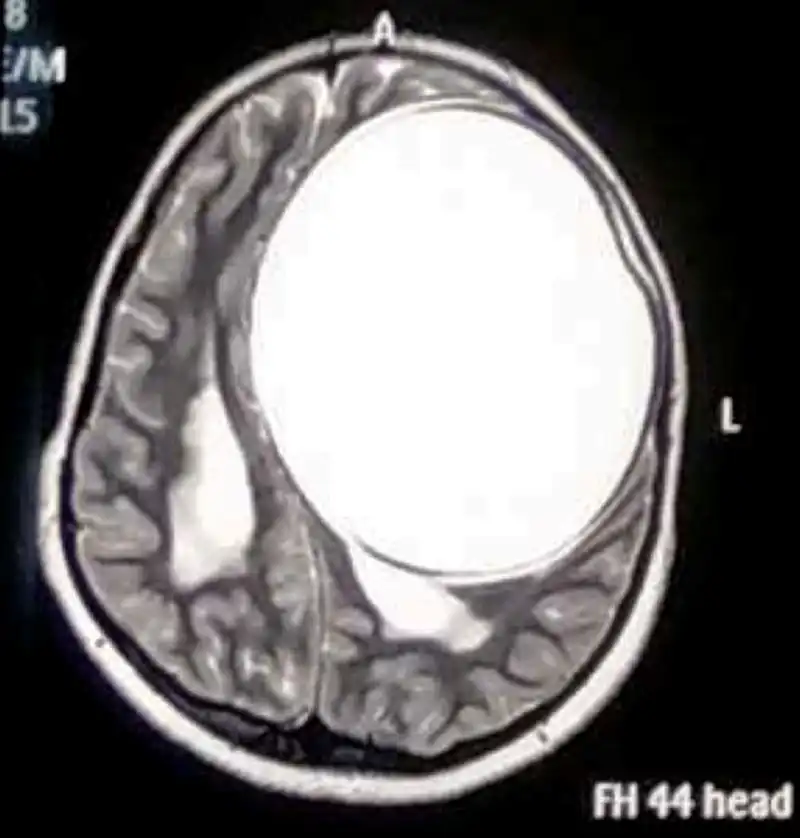

Тогда заботливый папа отвез дочь к нейрохирургу в Гандхидхам. Там и обнаружилось, что у девочки в голове развилась киста весом 675 грамм и габаритами 12,2 см x 11 см x 9,8 см. При этом никаких расстройств развития у девочки не было замечено.